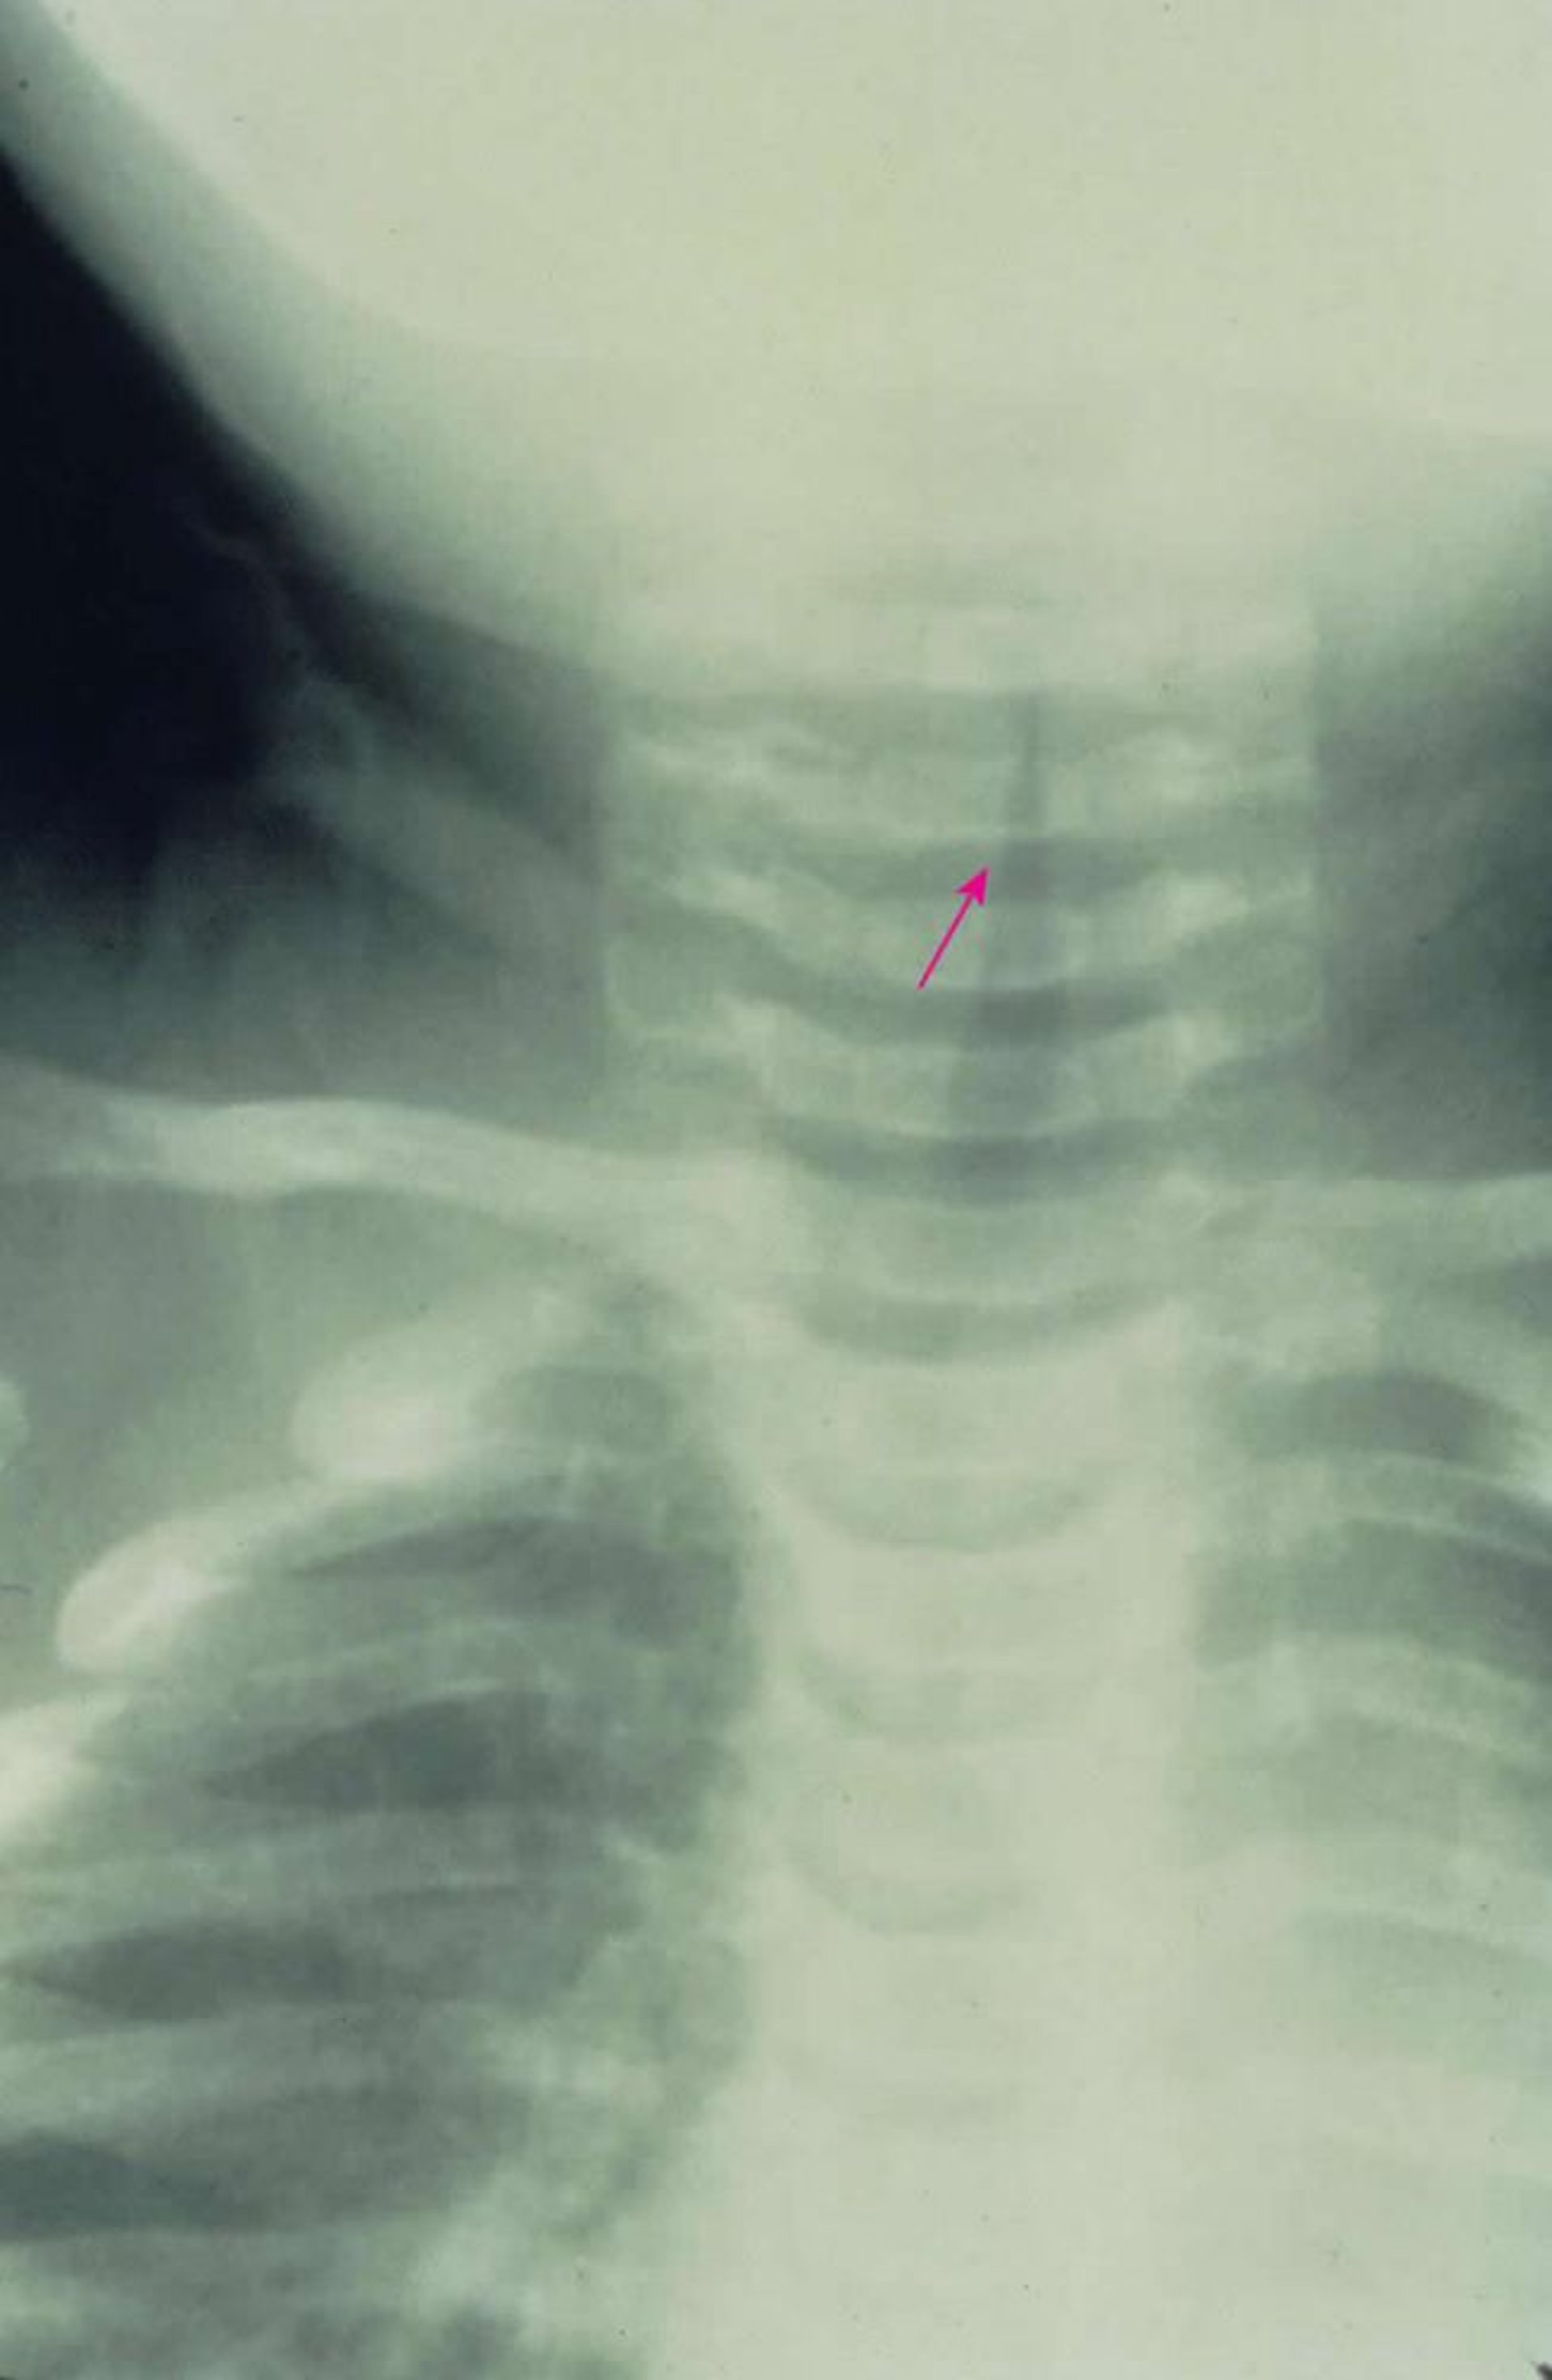

Laringotracheobronchite acuta sottoglottica

Questa RX antero-posteriore mostra un caratteristico restringimento sottoglottico della via aerea (segno della guglia) causato da laringotracheobronchite acuta.